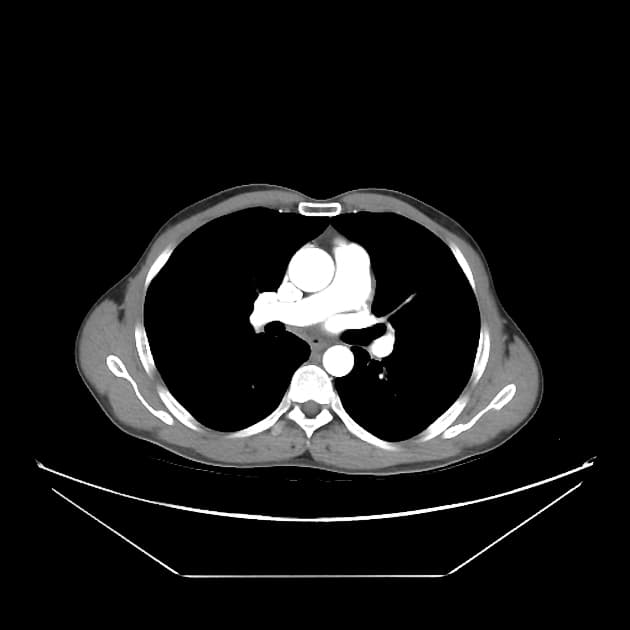

Tụy

Có khối kích thước 3 x 2 cm ở đầu tụy, tăng quang chậm và tiến triển, giảm tăng quang so với phần còn lại của tụy. Ống tụy chính phía trên giãn nhẹ, có hiện tượng tắc đột ngột như thấy trên MRCP gần đây. Không có vôi hóa tụy. Không thấy hình ảnh tắc mật (no evidence of biliary obstruction).

Khối lan xuống dưới vào mạc treo ruột non. Có hẹp nặng khu trú động mạch mạc treo tràng trên (SMV). Tiếp xúc giữa khối và SMV trên đoạn dài 42 mm. Tiếp xúc giữa khối và tĩnh mạch cửa trên đoạn dài 25 mm. Có xâm lấn nhánh tá tràng đầu tiên và thứ hai. Trục tạng, động mạch gan, động mạch mạc treo tràng trên thông thoáng. Động mạch vị tá tràng (GDA) bị bao quanh.

Hình ảnh học gợi ý ung thư biểu mô tuyến đầu tụy (pancreatic head adenocarcinoma), về mặt giải phẫu ở mức giới hạn có thể cắt bỏ được do có xâm lấn SMV và các nhánh tá tràng.

Ung thư biểu mô tuyến tụy - có thể cắt bỏ được ở mức giới hạn (borderline resectable)